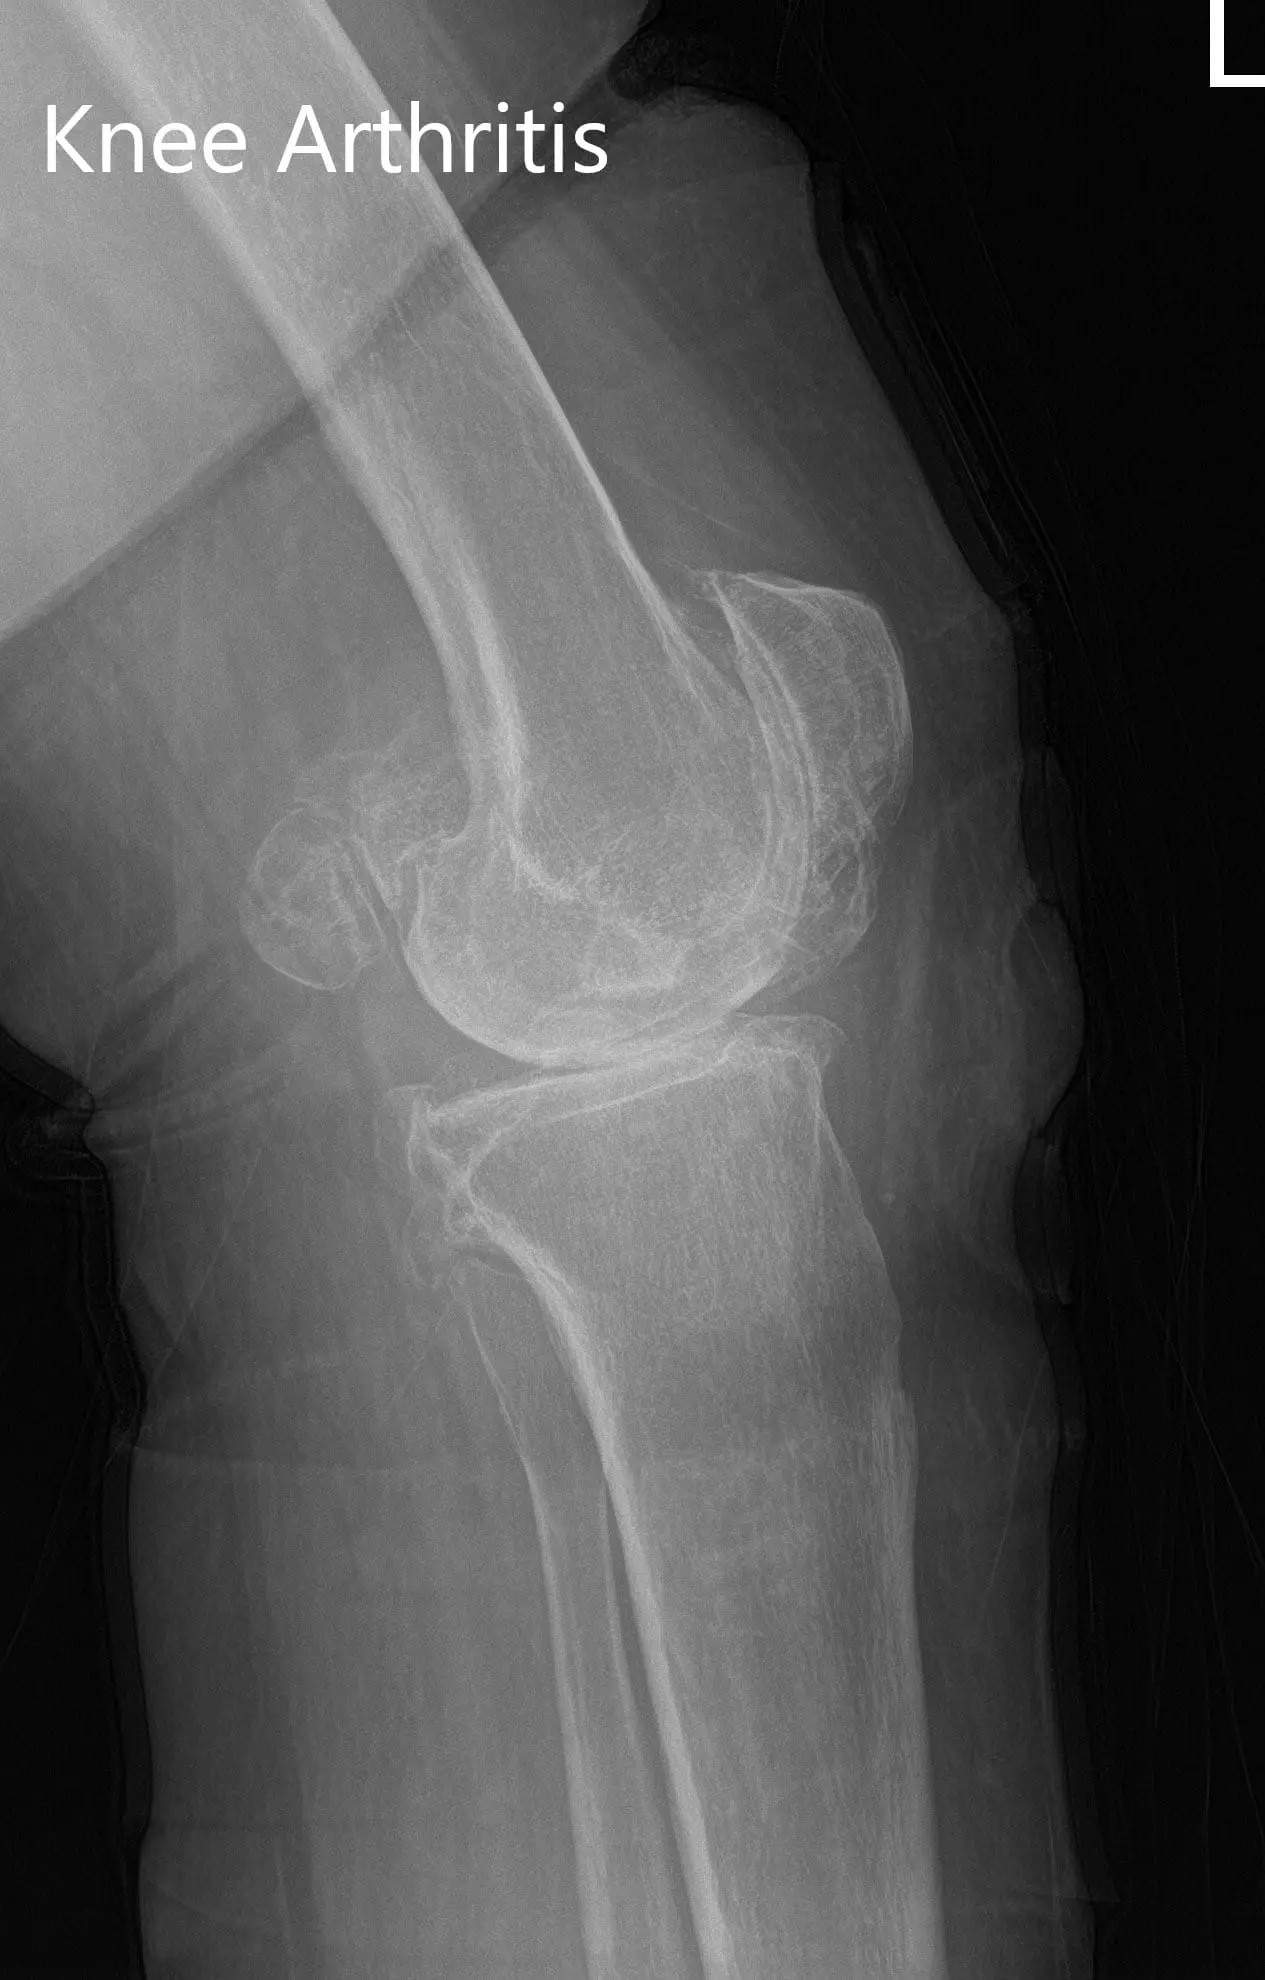

Preoperative X-ray of the left knee showing AP and lateral views